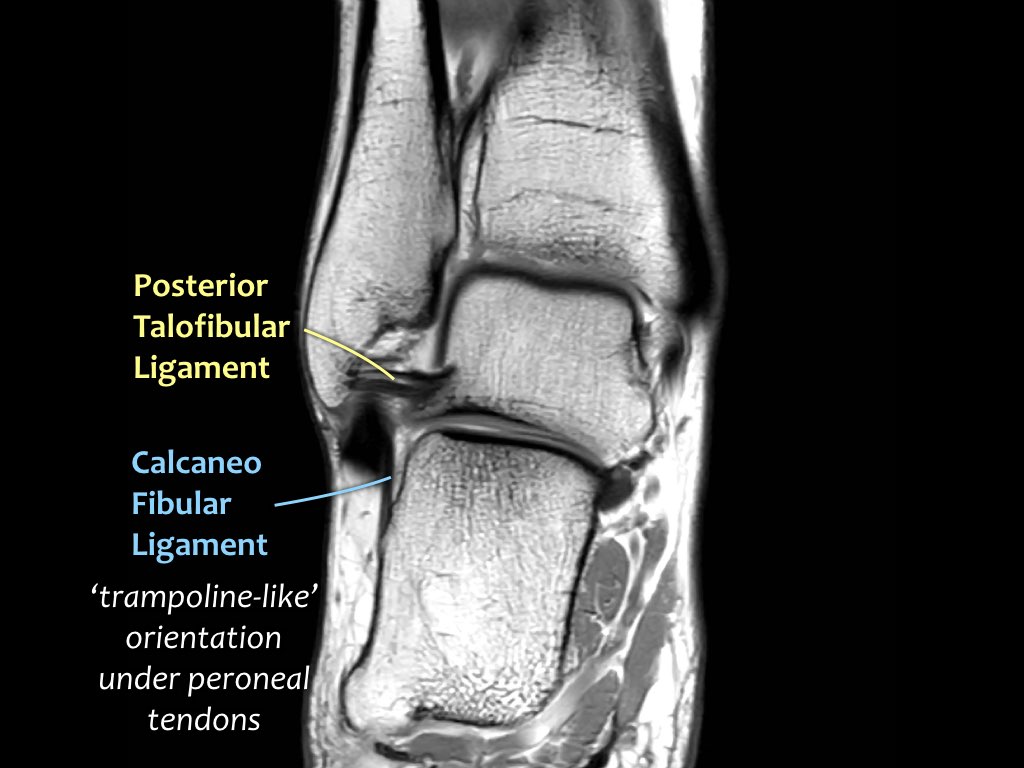

Có ba dây chằng ở phía ngoài:

- Dây chằng sên mác trước (anterior talofibular ligament – ATFL)

- Dây chằng gót mác (calcaneofibular ligament – CFL)

- Dây chằng sên mác sau (posterior talofibular ligament – PTFL).

Dây chằng ATFL chạy từ mắt cá ngoài ra phía trước đến bờ ngoài của xương sên.

Dây chằng này có hướng nằm ngang và được quan sát rõ nhất trên ảnh cắt ngang.

Đây là dây chằng bị tổn thương thường gặp nhất ở cổ chân và cũng là dây chằng đầu tiên bị tổn thương ở phía ngoài.

Điều này có nghĩa là khi dây chằng CFL hoặc PTFL bị tổn thương, rất có khả năng dây chằng ATFL cũng đã bị tổn thương.